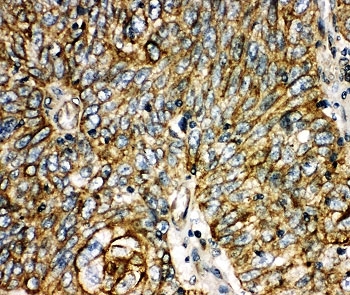

Aquaporin 6 is a protein in humans that is encoded by the AQP6 gene. The aquaporins (AQPs) are a family of water-transporting proteins that facilitate osmotically driven water movement across cell plasma membranes. Unlike other aquaporins, AQP6 functions not as a water channel but as an anion-selective channel. Single-channel analyses have shown AQP6 to flicker rapidly between closed and open status.

An amino acid sequence from the C-terminus of human Aquaporin 6 (EPLKKESQPGSGAVEMESV) was used as the immunogen for this Aquaporin 6 antibody.